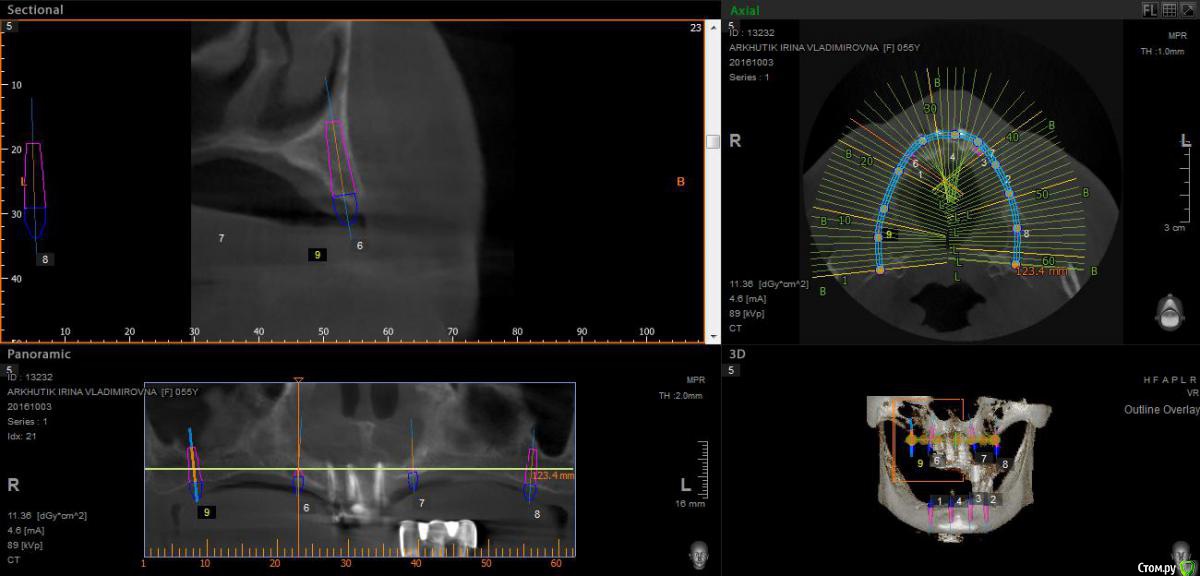

Rusty Опубликовано 5 октября, 2016 Поделиться Опубликовано 5 октября, 2016 Добрый день. К ортопеду обратилась пациентка 55-60 лет с такой ситуацией. Пришла с дочкой, дочь с мамой настаивали на несьемной конструкции, ортопед отправил на кт и вот. Не хочу планировать ей много хирургии, оцените и мой план пожалуйста и буду рад услышать советы по реабилитации пациента. По сути да) просто искал место куда есть возможность поставить, ортопед говорит тогда балка либо локаторы Ссылка на комментарий

Nazim_NV86 Опубликовано 5 октября, 2016 Поделиться Опубликовано 5 октября, 2016 На н/ч балка? Какие измерения в дист отделах? На в/ч мало четырёх. По три бы. Ссылка на комментарий

Rusty Опубликовано 5 октября, 2016 Автор Поделиться Опубликовано 5 октября, 2016 На н/ч балка? Какие измерения в дист отделах? На в/ч мало четырёх. По три бы.На н/ч балка, в дистальных отделах над каналом около 3мм. На вч условий для установки больше 4 не нашел) Ссылка на комментарий

Nazim_NV86 Опубликовано 6 октября, 2016 Поделиться Опубликовано 6 октября, 2016 Попробуйте на вч поискать ещё возможность хотя бы по Палаччи поставить. Ссылка на комментарий

Nazim_NV86 Опубликовано 6 октября, 2016 Поделиться Опубликовано 6 октября, 2016 А на низ кроме блоков больше рабочих методов не вижу. Ссылка на комментарий